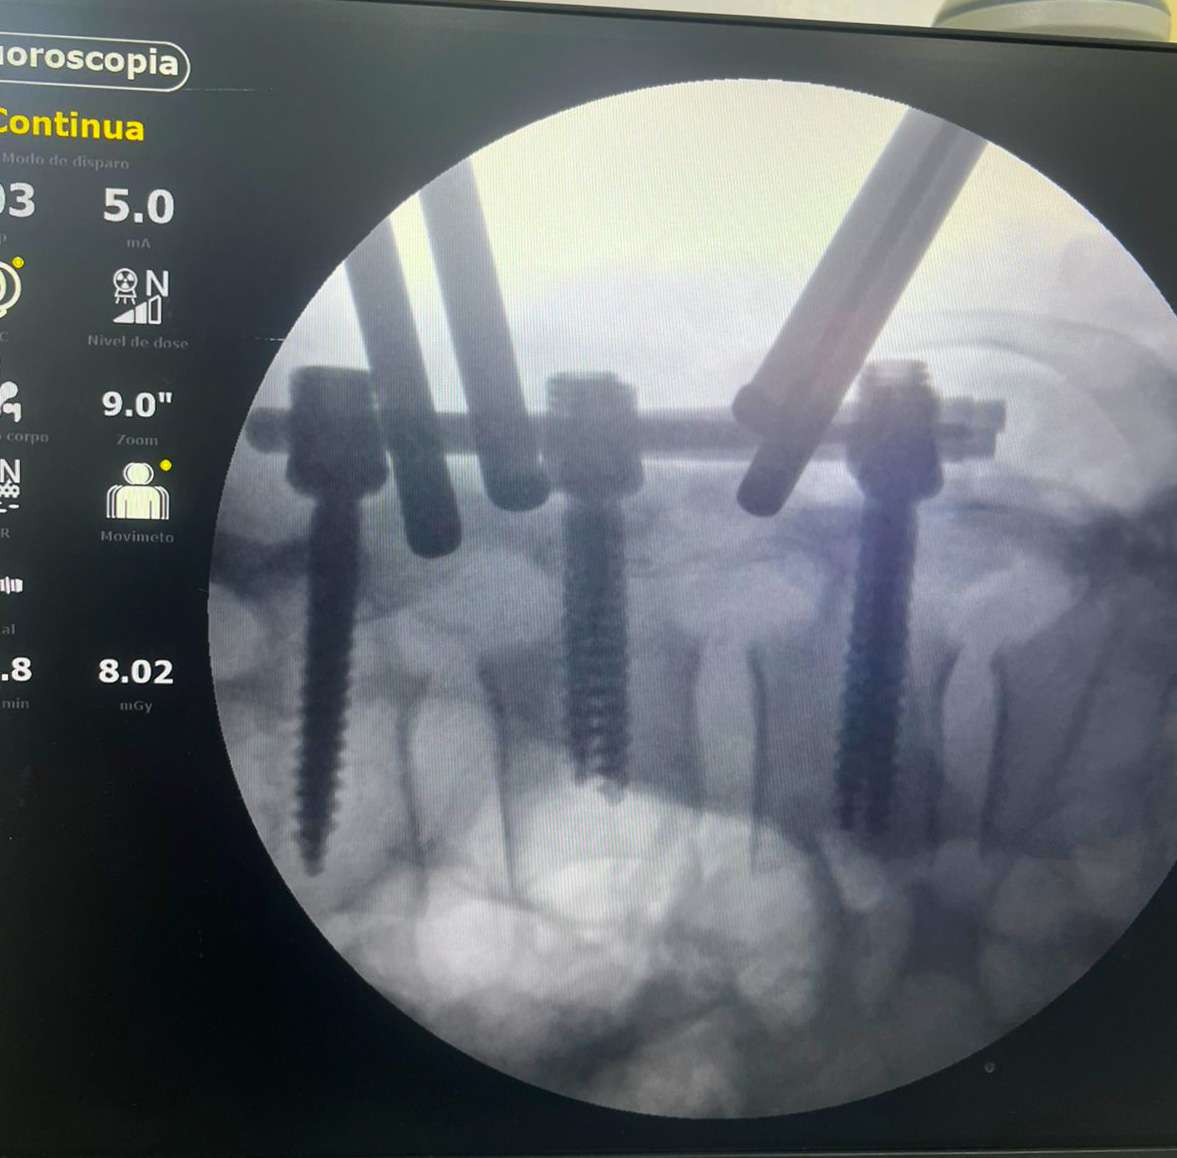

O procedimento, que durou 1h45, foi conduzido pelos ortopedistas especialistas em coluna, doutor Marlon Mendonça e Paulo Splenger, com apoio da equipe de trauma da unidade. Segundo o médico, a cirurgia transcorreu com sucesso e sem intercorrências. “O paciente chegou lúcido à UTI e já estava conversando após o procedimento. A expectativa agora é acompanhar a evolução neurológica, que depende do tempo e da resposta do organismo”, explicou doutor Marlon.

A intervenção teve como objetivo a descompressão da medula e a estabilização da coluna, medidas urgentes para minimizar os danos causados pelo trauma. “É um marco. Iniciamos um novo capítulo para o hospital, com a realização de cirurgias de alta complexidade que antes não eram possíveis. Isso representa mais qualidade, mais dignidade e menos sofrimento para os nossos pacientes”, afirmou doutor Paulo Splenger.